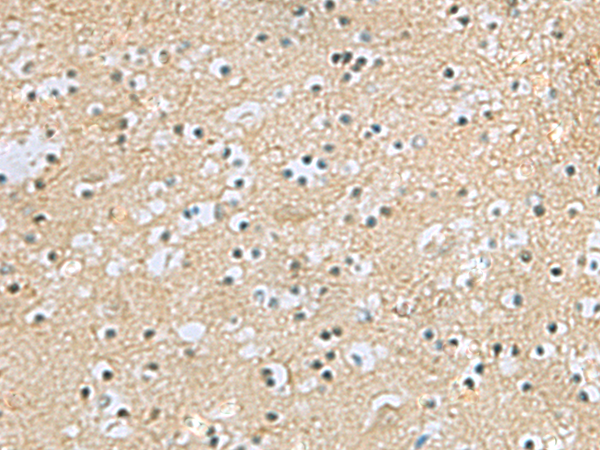

IHC positive control: |

Human brain |

IHC Recommend dilution: |

25-50 |